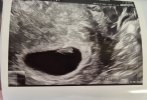

Ja po wizycie. Jest mały ktosiek z bijącym serduszkiem:)

Załączniki

• 20251019_143300.jpg

20251019_143300.jpg

957 KB · Wyświetleń: 31